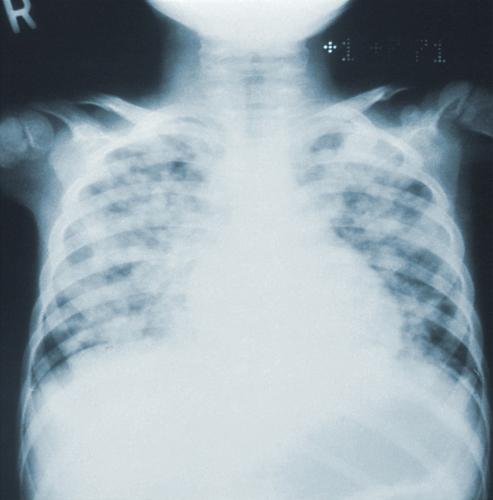

폐렴 전염: 폐렴은 감염성 질환으로, 주로 38도 이상의 고열, 누런 가래와 심한 기침 등이 나타납니다. 이러한 증상이 나타날 경우, 많은 사람들이 일반적으로 감기로 오해하고 크게 신경쓰지 않게 됩니다. 하지만, 폐렴은 전염성이 높은 질병이기 때문에 초기 증상을 제대로 파악하고 예방하는 것이 매우 중요합니다.

폐렴은 주로 비인두감염으로 전염되기 때문에 주의가 필요합니다. 폐렴을 일으키는 원인균에 의해 전염되고 감염됩니다. 따라서, 알맞은 예방책과 격리 조치가 필요합니다.